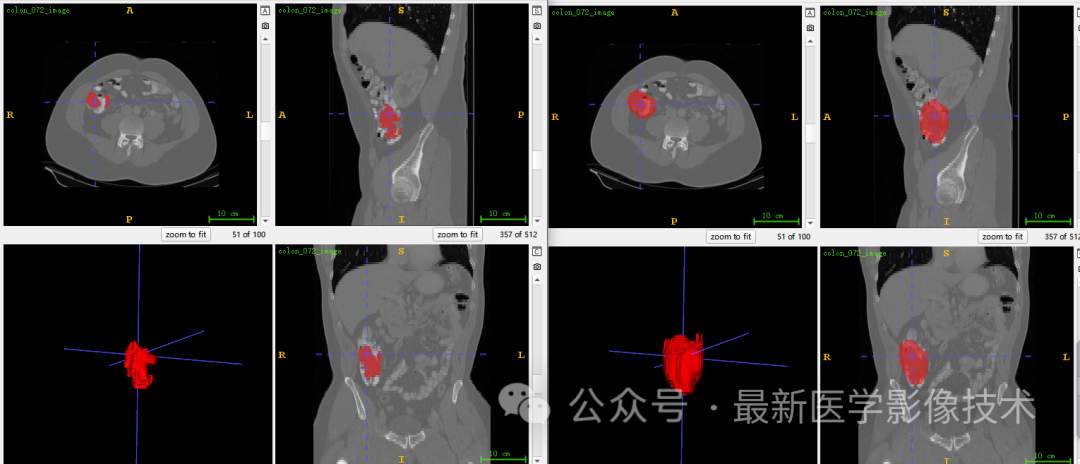

6、测试集分割结果